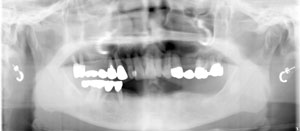

‚j.M.‚³‚ñ @48Î@’j«@ ‰ïŽÐ–ðˆõ   Žèp“ú

‚Q‚O‚P‚T”N  ‚PŒŽ ‚Q‚R“úi‹àj@㉺Š{ ƒm[ƒxƒ‹ƒKƒCƒhŽg—p@Ö¬“à’ÁÖ@•¹—p@

@@@@@@@@@—¼‘¤ƒ‰ƒeƒ‰ƒ‹‚©‚çƒTƒCƒiƒXƒŠƒtƒg‚µ‚ÄA‚`‚s‚aiƒI[ƒgƒgƒD[ƒXƒ{[ƒ“jŽg—pƒIƒyAŠO—ˆ‰Ç—á

@@@@@@@@@ãŠ{ ‚X–{@ @ƒvƒƒr‘¦Žž‘•’…@@@@@@@@@@@@@@@@@@@@@@@‰ºŠ{ ‚U–{@ @ƒvƒƒr‘¦Žž‘•’…

@@@@@@@@@@@”‚P‚W@F@Bmk MK‡V Ht@RP‚SD‚O  ~  ‚P‚OD‚O ‚‚

@@@@@@@@@@@”‚S‚U@F@Bmk MK‡V Ht@RP‚RD‚V‚T  ~‚P‚RD‚O ‚‚

@@@@@@@@@@@”‚P‚S@F@Bmk MK‡V Ht@RP‚RD‚V‚T ~ ‚P‚TD‚O ‚‚@@@@@@@@@@@”‚S‚S@F@Bmk MK‡V Ht@RP‚RD‚V‚T  ~‚P‚RD‚O ‚‚

@@@@@@@@@@@”‚P‚R@F@Bmk MK‡V Ht@RP‚RD‚V‚T  ~ ‚P‚OD‚O ‚‚@@@@@@@@@@ ”‚S‚Q@F@Bmk MK‡V Ht@RP‚RD‚V‚T  ~‚P‚RD‚O ‚‚

@@@@@@@@@@@”‚P‚P@F@Bmk MK‡V Ht@RP‚SD‚O  ~  ‚P‚TD‚O ‚‚@@@@@@@@@@@”‚R‚Q@F@Bmk MK‡V Ht@RP‚RD‚V‚T  ~‚P‚RD‚O ‚‚

@@@@@@@@@@@”‚Q‚P@F@Bmk MK‡V Ht@RP‚RD‚V‚T  ~ ‚P‚TD‚O ‚‚@@@@@@@@@@ ”‚R‚T@F@Bmk MK‡V Ht@RP‚SD‚O  ~ ‚P‚RD‚O ‚‚

@@@@@@@@@@@”‚Q‚Q@F@Bmk MK‡V Ht@RP‚RD‚V‚T ~ ‚P‚TD‚O ‚‚@@@@@@@@@@@”‚R‚U@F@Bmk MK‡V Ht@RP‚SD‚O  ~ ‚P‚RD‚O ‚‚

@@@@@@@@@@@”‚Q‚S@F@Bmk MK‡V Ht@RP‚SD‚O  ~  ‚P‚RD‚O ‚‚

@@@@@@@@@@@”‚Q‚V@F@Bmk MK‡V Ht@RP‚SD‚O  ~@ ‚WD‚T ‚‚

@@@@@@@@@@@”‚Q‚W@F@Bmk MK‡V Ht@RP‚SD‚O  ~ ‚P‚OD‚O ‚‚@